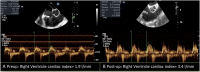

Tricuspid regurgitation in patients with left ventricular assist device (LVAD) has a significant impact on prognosis and quality of life, and its effects on liver and renal function could negatively impact planned heart transplantation. The aim of the present case is to report the feasibility and the clinical impact of tricuspid transcatheter edge-to-edge repair in LVAD patients as adjunctive bridge to transplantation strategy. A 59-year-old female patient previously treated with LVAD implantation (HeartMate III) and tricuspid valve repair with 32 mm rigid ring (Medtronic Contour 3D) as bridge to transplantation developed recurrence of significant tricuspid regurgitation with right ventricular decompensation needing inotropic support. Preoperative echo showed torrential tricuspid valve regurgitation Effective regurgitant orifice area(EROA 1.4 cm2 ) with suspicious of partial detachment of the prosthetic ring. The patient was successfully treated with transcatheter edge-to-edge repair with the MitraClip XTR device. Tricuspid regurgitation was reduced by 50% (postoperative EROA 0.7 cm2 ). She remained stable under continuous inotropic support with no other episodes of right ventricular decompensation and was successfully transplanted 30 days after the clipping procedure. Transcatheter treatment of tricuspid regurgitation in a patient with LVAD was an effective strategy to gain time and bridge the patient to heart transplantation.